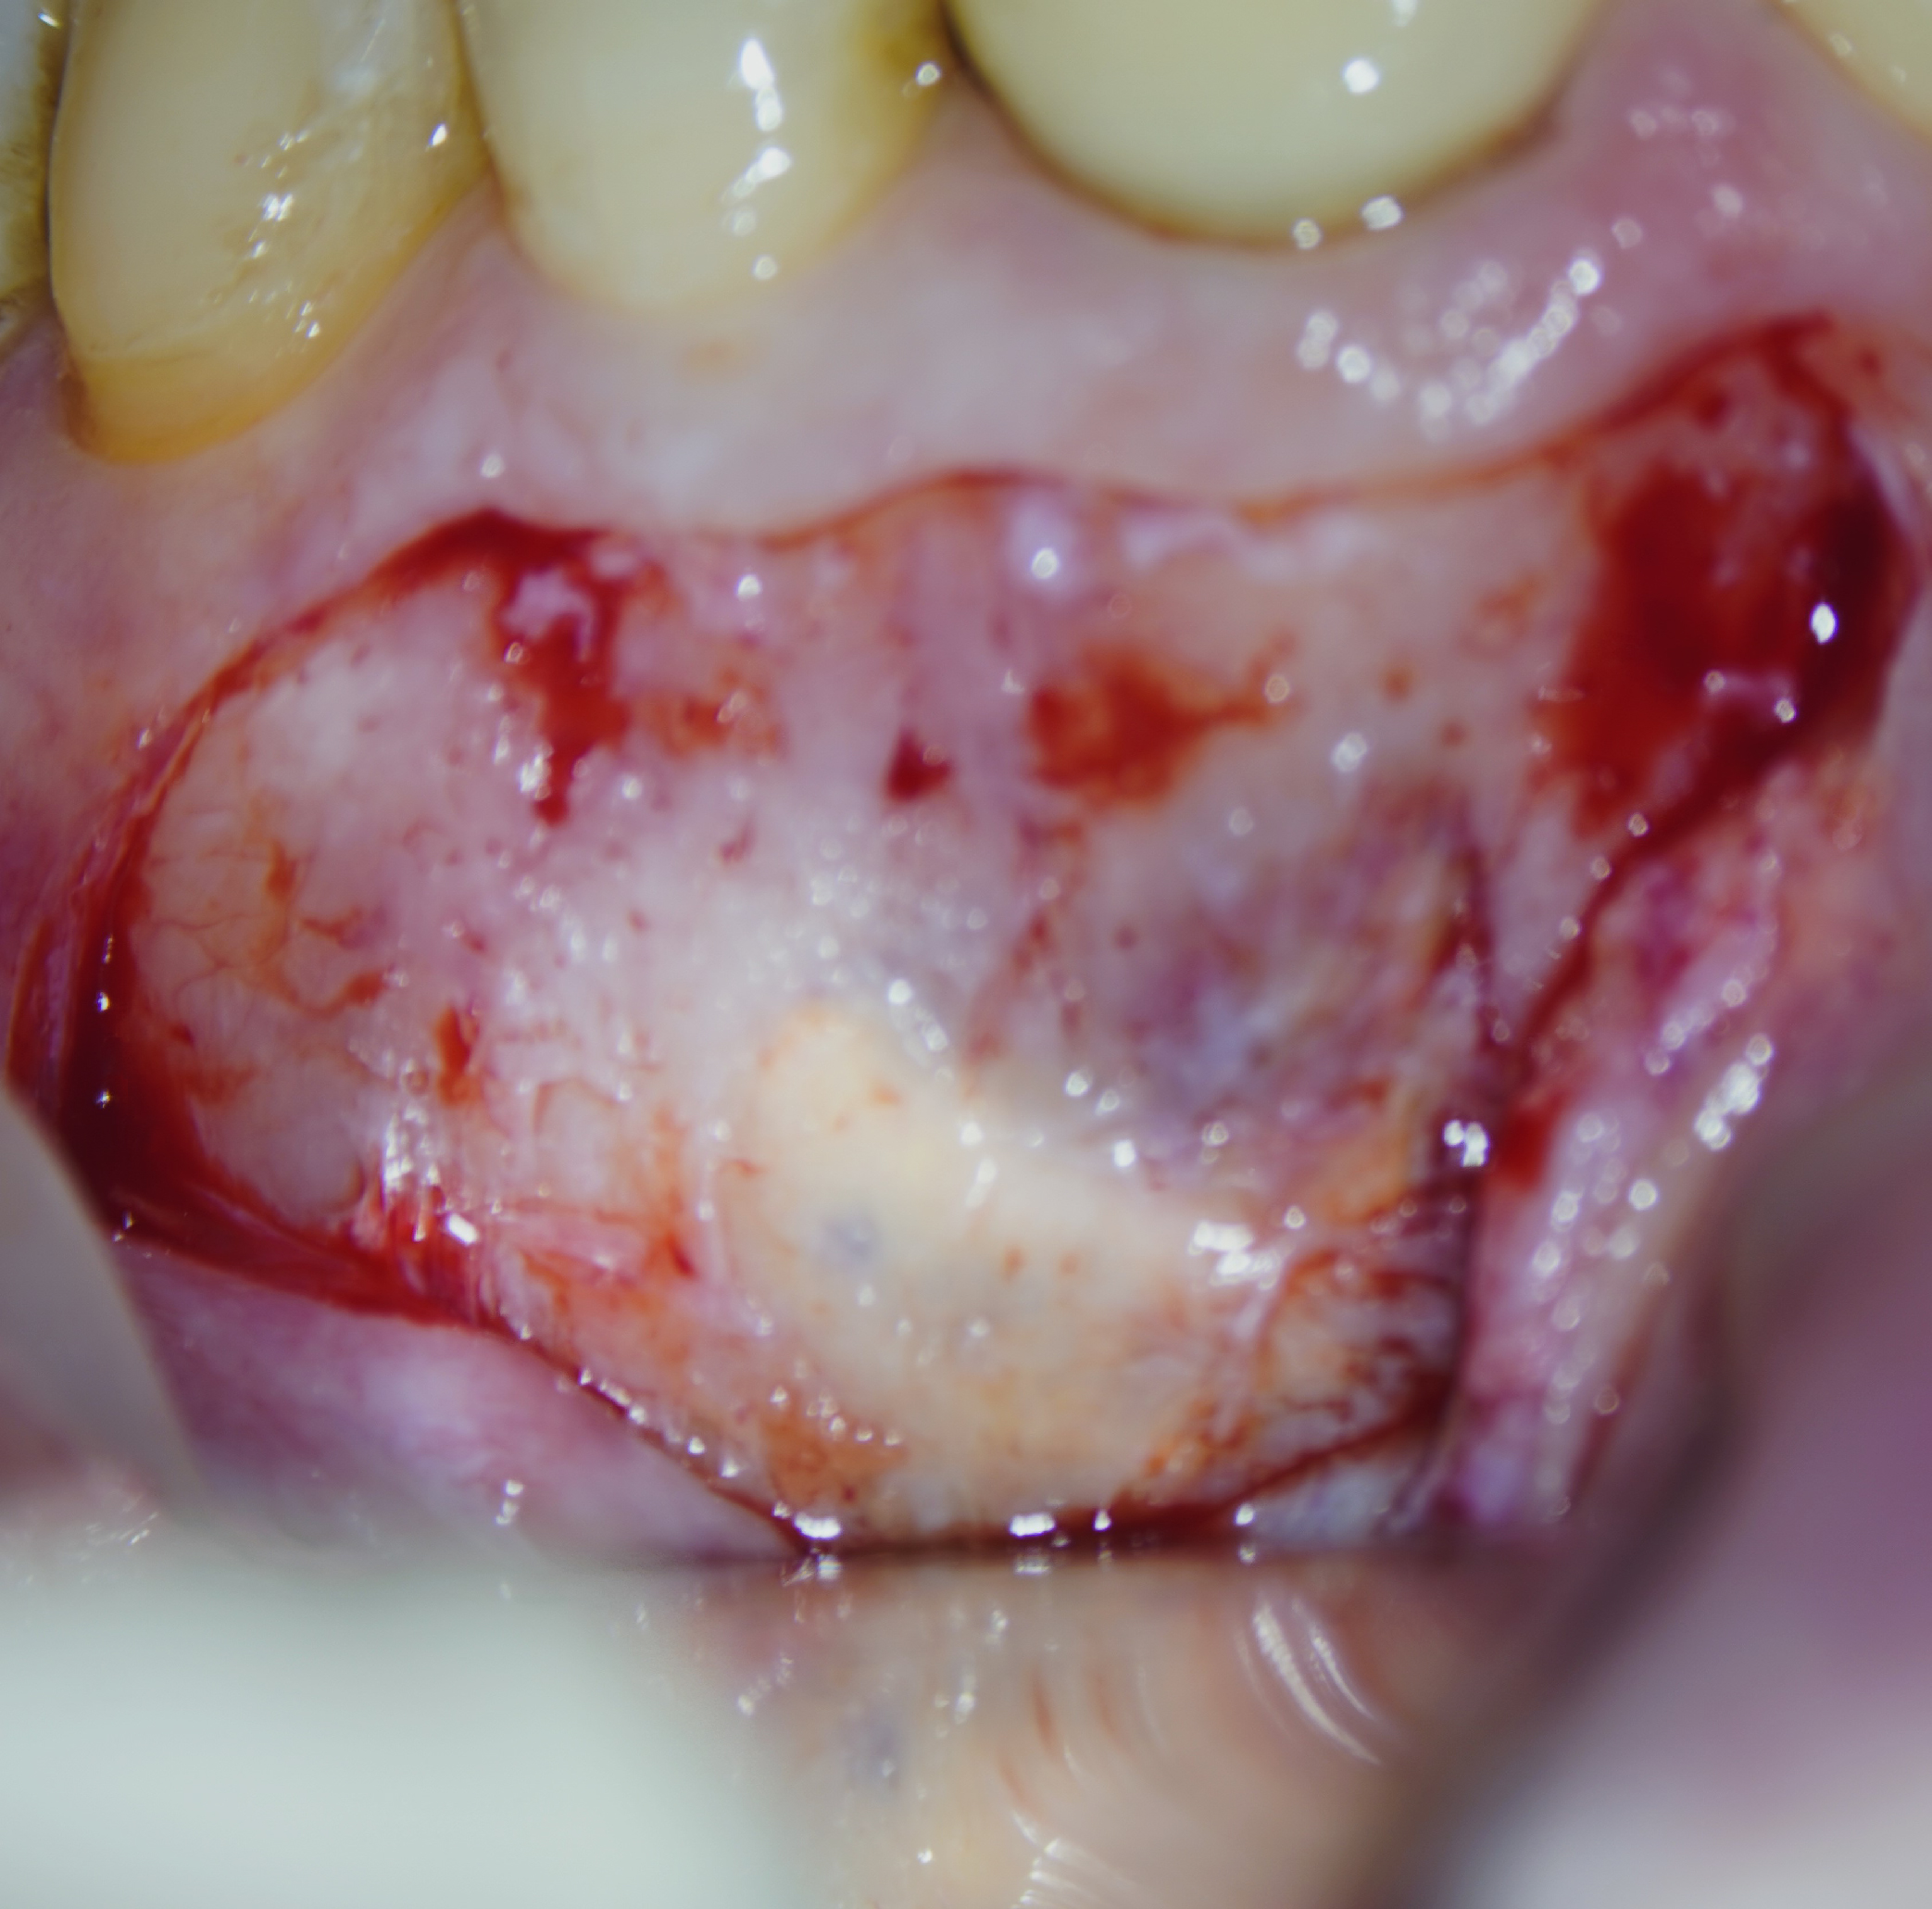

Imágenes del tratamiento

* Haz click sobre las imágenes para verlas a mayor tamaño y a color